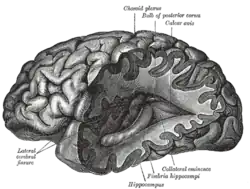

Work by Andreas Vesalius on human cadavers found problems with the Galenic view of anatomy. Vesalius noted many structural characteristics of both the brain and general nervous system during his dissections.[12] In addition to recording many anatomical features such as the putamen and corpus callosum, Vesalius proposed that the brain was made up of seven pairs of 'brain nerves', each with a specialized function. Other scholars furthered Vesalius' work by adding their own detailed sketches of the human brain.